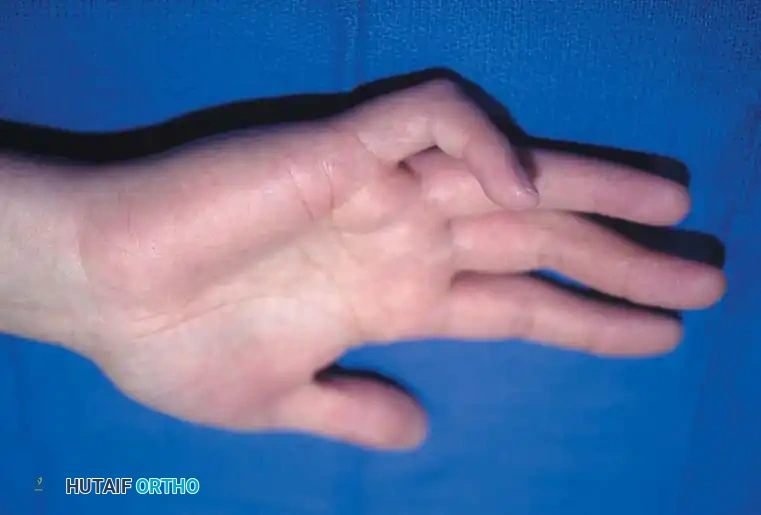

Clinical presentation of a congenital trigger thumb in a 2-year-old child, demonstrating the characteristic fixed flexion posture of the interphalangeal (IP) joint.

Prospective studies of over 5,765 newborns have failed to reveal a single case of congenital trigger thumb at birth, supporting the consensus that the condition is more accurately described as acquired in infancy. It is frequently unnoticed until the child reaches 1 to 2 years of age, presenting as a relatively fixed flexion posture of the interphalangeal (IP) joint.

Even with passive force, full extension of the IP joint may be impossible. The abnormal clicking or snapping that is the hallmark of adult trigger digits is rarely the presenting complaint in children.

Clinical photograph of classic camptodactyly, demonstrating an isolated flexion deformity of the proximal interphalangeal joint of the little finger.